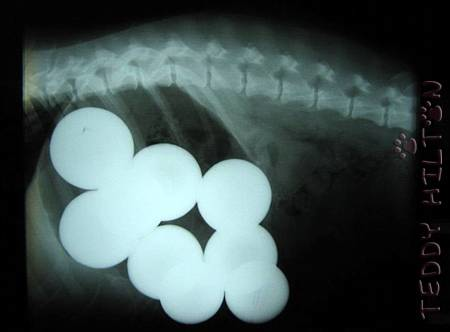

Эта оголодавшая собака проглотила 9 бильярдных шаров